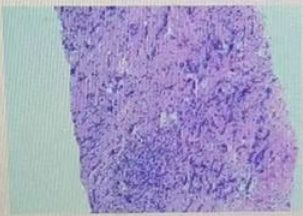

·病理

(右乳肿块穿刺病理):浸润性乳腺癌,非特殊类型(浸润性导管癌),Nottingham分级:2级,未见明确脉管内癌栓及神经侵犯。免疫组化结果:ER(约2%弱+),PR(约5%弱+),Her-2(3+),Ki67(约50%+)。

图5穿刺活检结果